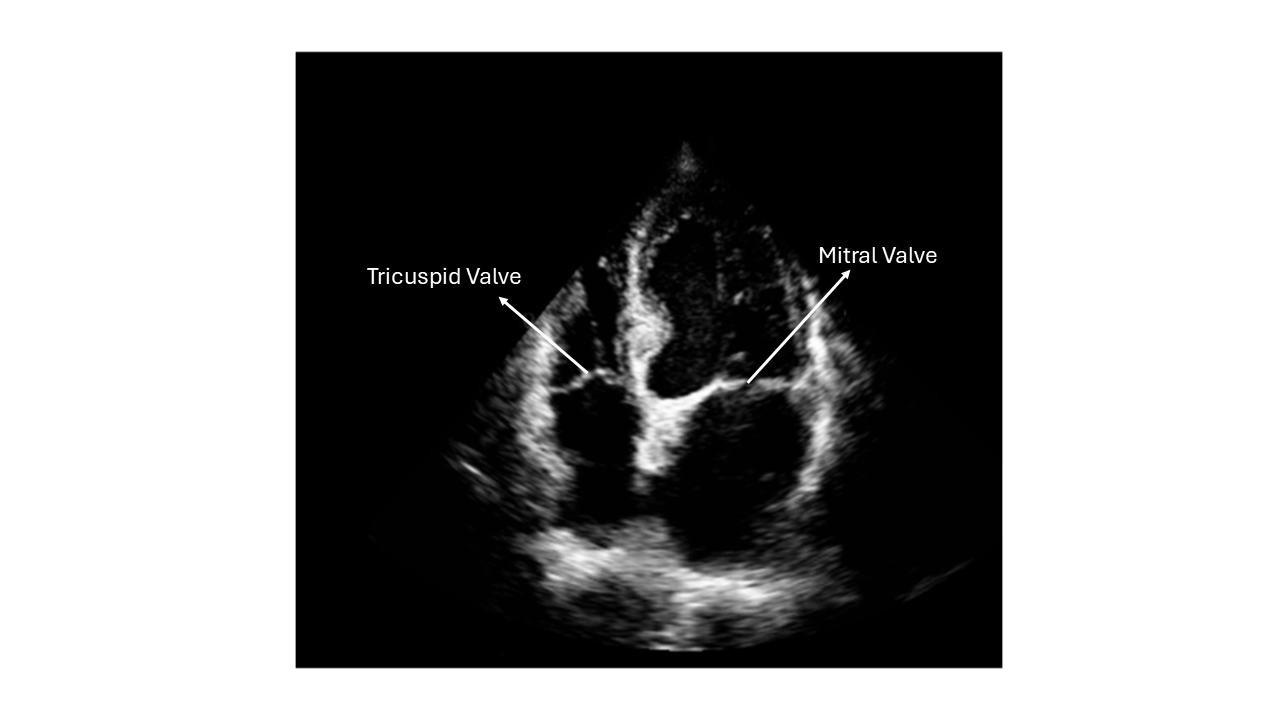

We are training an AI to automatically detect and assess the clarity of valve visibility in echocardiographic images, specifically in the apical four-chamber (A4C) view.

To achieve this, we are ranking images based on how clearly the mitral or tricuspid valves are visible — from the clearest to the least visible.

Visual Example

Valve Visibility Example